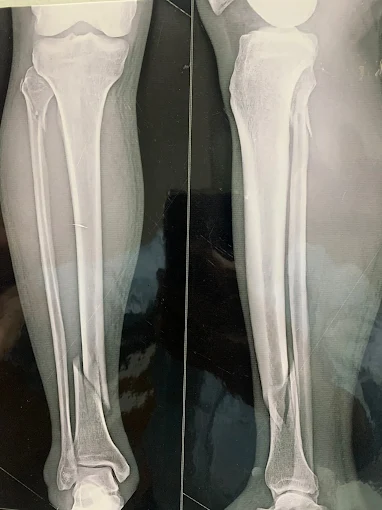

Trauma Surgery

Expert fracture and bone injury management with advanced surgical care

Fracture & Trauma Surgery

Expert management for complex fractures and trauma recovery

orthopaedic trauma

Comprehensive care for severe musculoskeletal injuries to restore stability and function